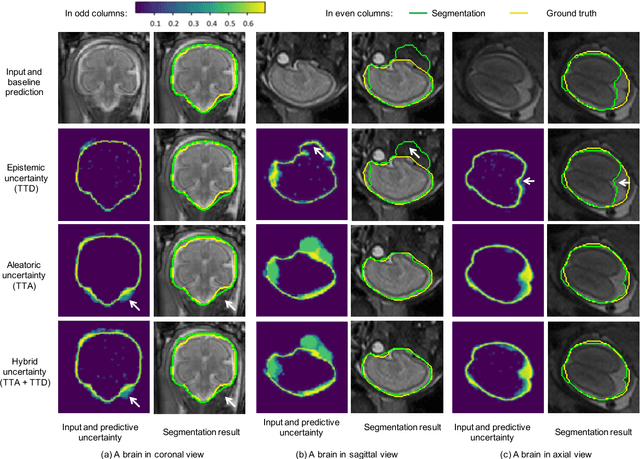

Abstract:Despite the state-of-the-art performance for medical image segmentation, deep convolutional neural networks (CNNs) have rarely provided uncertainty estimations regarding their segmentation outputs, e.g., model (epistemic) and image-based (aleatoric) uncertainties. In this work, we analyze these different types of uncertainties for CNN-based 2D and 3D medical image segmentation tasks. We additionally propose a test-time augmentation-based aleatoric uncertainty to analyze the effect of different transformations of the input image on the segmentation output. Test-time augmentation has been previously used to improve segmentation accuracy, yet not been formulated in a consistent mathematical framework. Hence, we also propose a theoretical formulation of test-time augmentation, where a distribution of the prediction is estimated by Monte Carlo simulation with prior distributions of parameters in an image acquisition model that involves image transformations and noise. We compare and combine our proposed aleatoric uncertainty with model uncertainty. Experiments with segmentation of fetal brains and brain tumors from 2D and 3D Magnetic Resonance Images (MRI) showed that 1) the test-time augmentation-based aleatoric uncertainty provides a better uncertainty estimation than calculating the test-time dropout-based model uncertainty alone and helps to reduce overconfident incorrect predictions, and 2) our test-time augmentation outperforms a single-prediction baseline and dropout-based multiple predictions.